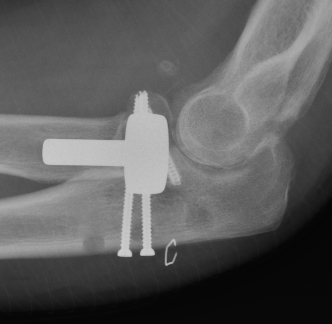

Radial head replacement with lasso fixation of small coronoid fragment